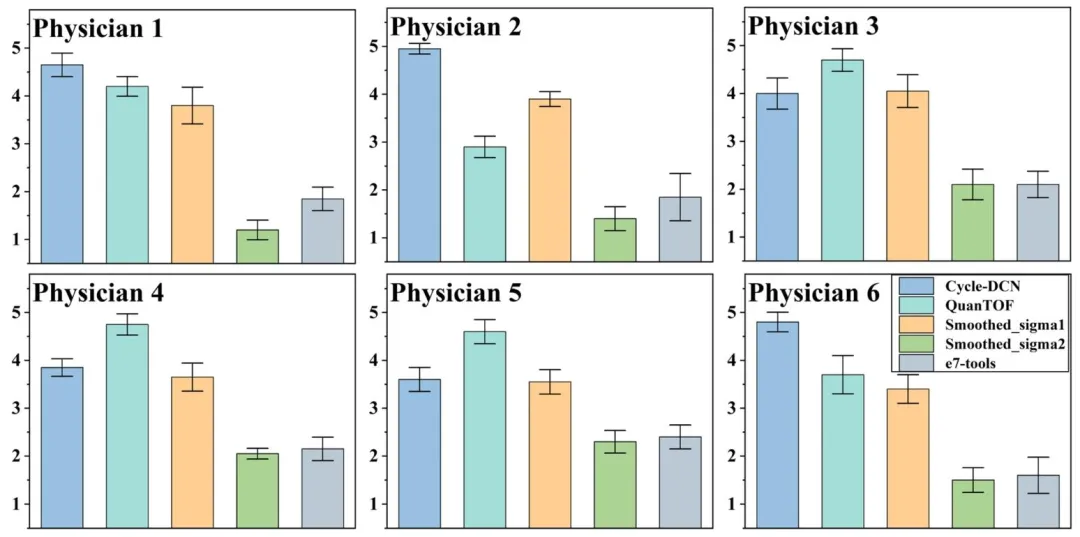

Fig. 9. The scoring results for real low-dose images processed using different algorithms on the randomly selected 20 cases in the test dataset.

图9 五位医师对测试数据集中随机选取的20个病例,经不同算法处理后的真实低剂量图像的评分结果。